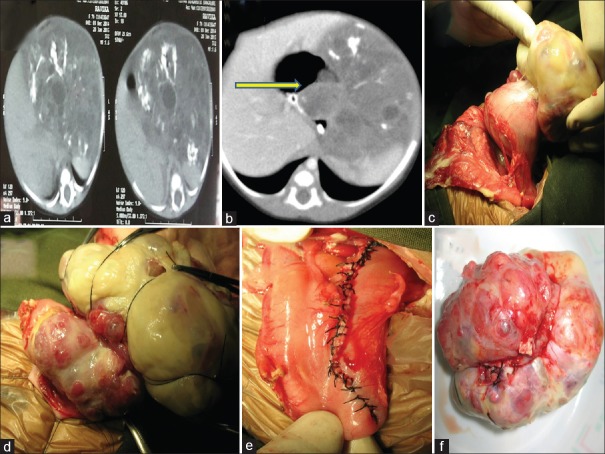

| Figure 1:(a) Computed tomography scan picture of mature gastric teratoma with areas of chunky calcifications. (b) Computed tomography scan picture of immature gastric teratoma showing heterogeneous tumor with specks of calcification; yellow-colored arrow pointing at intragastric component. (c) Ruptured immature gastric teratoma with slough over the surface, arising from anterior wall of stomach. (d) Intraoperative picture showing intragastric component. (e) Suture line after complete excision, extending from gastroesophageal junction to antrum. (f) Excised gastric teratoma

A 1-month-old female baby born by full-term cesarean section, with birth weight of 2.8 kg, presented to us with progressive abdominal distention with breathing difficulty for 5 days. The routine antenatal USG scans were normal. Postnatal USG revealed large intraabdominal tumor of solid and cystic components, and CECT scan revealed large intraabdominal tumor with solid and cystic lesion having specks of calcification [Figure [Figure1b].1b]. At presentation, the baby had abdominal distention with respiratory difficulty. Serum beta HCG, AFP, and LDH were within normal range. On laparotomy, we found variegated mass of 10 cm × 8 cm arising from the anterior wall of stomach extending up to GE junction having endogastric as well exogastric component with tumor ruptured and gross peritoneal spillage [Figure [Figure1c,1c, ,dd and andf].f]. The tumor was resected with the margin of 1 cm and the resultant defect from GEJ to antrum was closed in two layers [Figure [Figure1e].1e]. The peritoneal cavity was washed thoroughly with normal saline. Postoperative period was uneventful. HPE revealed multiple tubules of varying sizes lined by primitive neuroepithelium which contributed to <10 href="https://www.ncbi.nlm.nih.gov/pmc/articles/PMC5759085/figure/F2/" target="figure" class="fig-table-link figpopup" rid-figpopup="F2" rid-ob="ob-F2" co-legend-rid="lgnd_F2" xss=removed>[Figure2c2c and andd].d]. Baby is doing well at a year of follow-up.

Gastric teratomas (GTs) are rare tumors and constitute 1% of all the teratomas in the body. Most patients present in the neonatal period with male predilection. There are only nine reported female infants with GTs in the English literature till 2004, and in our series, one was a female neonate. Only about 112 cases of GTs are recorded till 2012, of which <15 href="https://www.ncbi.nlm.nih.gov/pmc/articles/PMC5759085/#ref1" rid="ref1" class=" bibr popnode tag_hotlink tag_tooltip" id="__tag_659254240" role="button" aria-expanded="false" aria-haspopup="true" xss=removed>1] Typical presenting symptoms are abdominal lump, distension, and vomiting, but tumors with intramural extension presenting with gastrointestinal bleeding and gastric perforation have also been reported in literature.[3] GT presents as a palpable mass in 75% and/or abdominal distension in 56%.[2] Other rare presentations are peritonitis secondary to gastric perforation and tumor rupture.[4] In our series, case 1 presented with antenatal diagnosis of tumor and presented with abdominal distention. Case 2 presented with respiratory distress and early peritonitis which was unusual. Both of our patients had intragastric component along with major extragastric component and surprisingly had no bleeding or obstruction [Figure [Figure1b1b and andd].d]. Most of these tumors arise from the greater curvature and posterior wall of the stomach.[3] The growth of GTs has been exogastric in 65%, endogastric in 9%, and endogastric/exogastric in 26% of reported cases;[2,5,6]. both of our patients had the tumor arising from the lesser curvature with extension to GEJ which was not commonly reported. Case 2 had tumor which was arising from the anterior wall of the stomach in continuation from the lesser curvature which in itself is a rarity [Figure 1c].

Preoperative evaluation will require CECT abdomen and tumor markers apart from routine USG. In most cases, tumor markers are elevated, and they can be used as a prognostic marker in the follow-up. As a general approach, complete surgical excision is sufficient for mature teratoma and Grade 1 and 2 immature teratoma if serum AFP and beta HCG values are within normal range for the age and there is no malignant germ cell element. Elevated serum AFP levels may be the only alerting sign of the presence of malignant yolk sac component. However, the diagnostic utility of these oncofetal proteins is less in young infants because of the physiologically elevated levels.[5] In our series also, the tumor markers were within the age range. CECT abdomen did reveal a large heterogeneous mass arising from the retroperitoneum to the left of abdomen [Figure 1a and andb].b]. In both the patients, the gastric origin of the tumor was not identified preoperatively but was suspected in view of close proximity of the stomach to the tumor.

Complete surgical excision will result in good long-term outcome.[3] Mature teratoma and immature teratoma Grade 1 and 2 will only require total excision and no adjuvant therapy.[5] In both of our babies, we were able to achieve complete excision with rim of normal stomach. In case 2, the tumor was involving the GEJ, and the anterior esophageal defect was repaired with fundal flap covering [Figure 1e]. Both the patients had uneventful recovery.